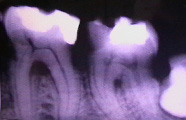

imag. rad. 44 in eruptie

molar de minte inclus